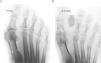

Técnica quirúrgicaTodas las intervenciones se realizaron bajo anestesia regional mediante bloqueo poplíteo, según la técnica descrita por De Prado9: a través de una mínima incisión dorsal realizada con bisturí de cirugía percutánea, localizada proximal al pliegue interdigital y en dirección oblicua de 45° respecto al plano del suelo, se contacta con la cara dorsal del cuello del metatarsiano que se desea osteotomizar. Se introduce la raspa de cirugía percutánea para desperiostizar levemente la zona bajo control radiológico. Con una fresa tipo Shannon se realiza la osteotomía según un plano oblicuo de dorsal y distal a plantar y proximal; en todos los casos se confirma la osteotomía mediante control radiológico traccionando los dedos (fig. 1). Luego se sutura la entrada de la fresa mediante un punto, se aplica un vendaje tipo cincha metatarsiana con venda elástica y se autoriza la carga completa de forma inmediata con un zapato de suela plana.

La consolidación radiológica se consiguió en todos los casos y para esto se precisó un tiempo medio de 8,8 semanas (rango de 6 a 15); 6 pies (14%) se consolidaron en menos de 2 meses, 35 pies (80%) se consolidaron en un período de 2 a 3 meses y sólo 3 pies (6%) precisaron más de 3 meses para consolidarse (fig. 2).